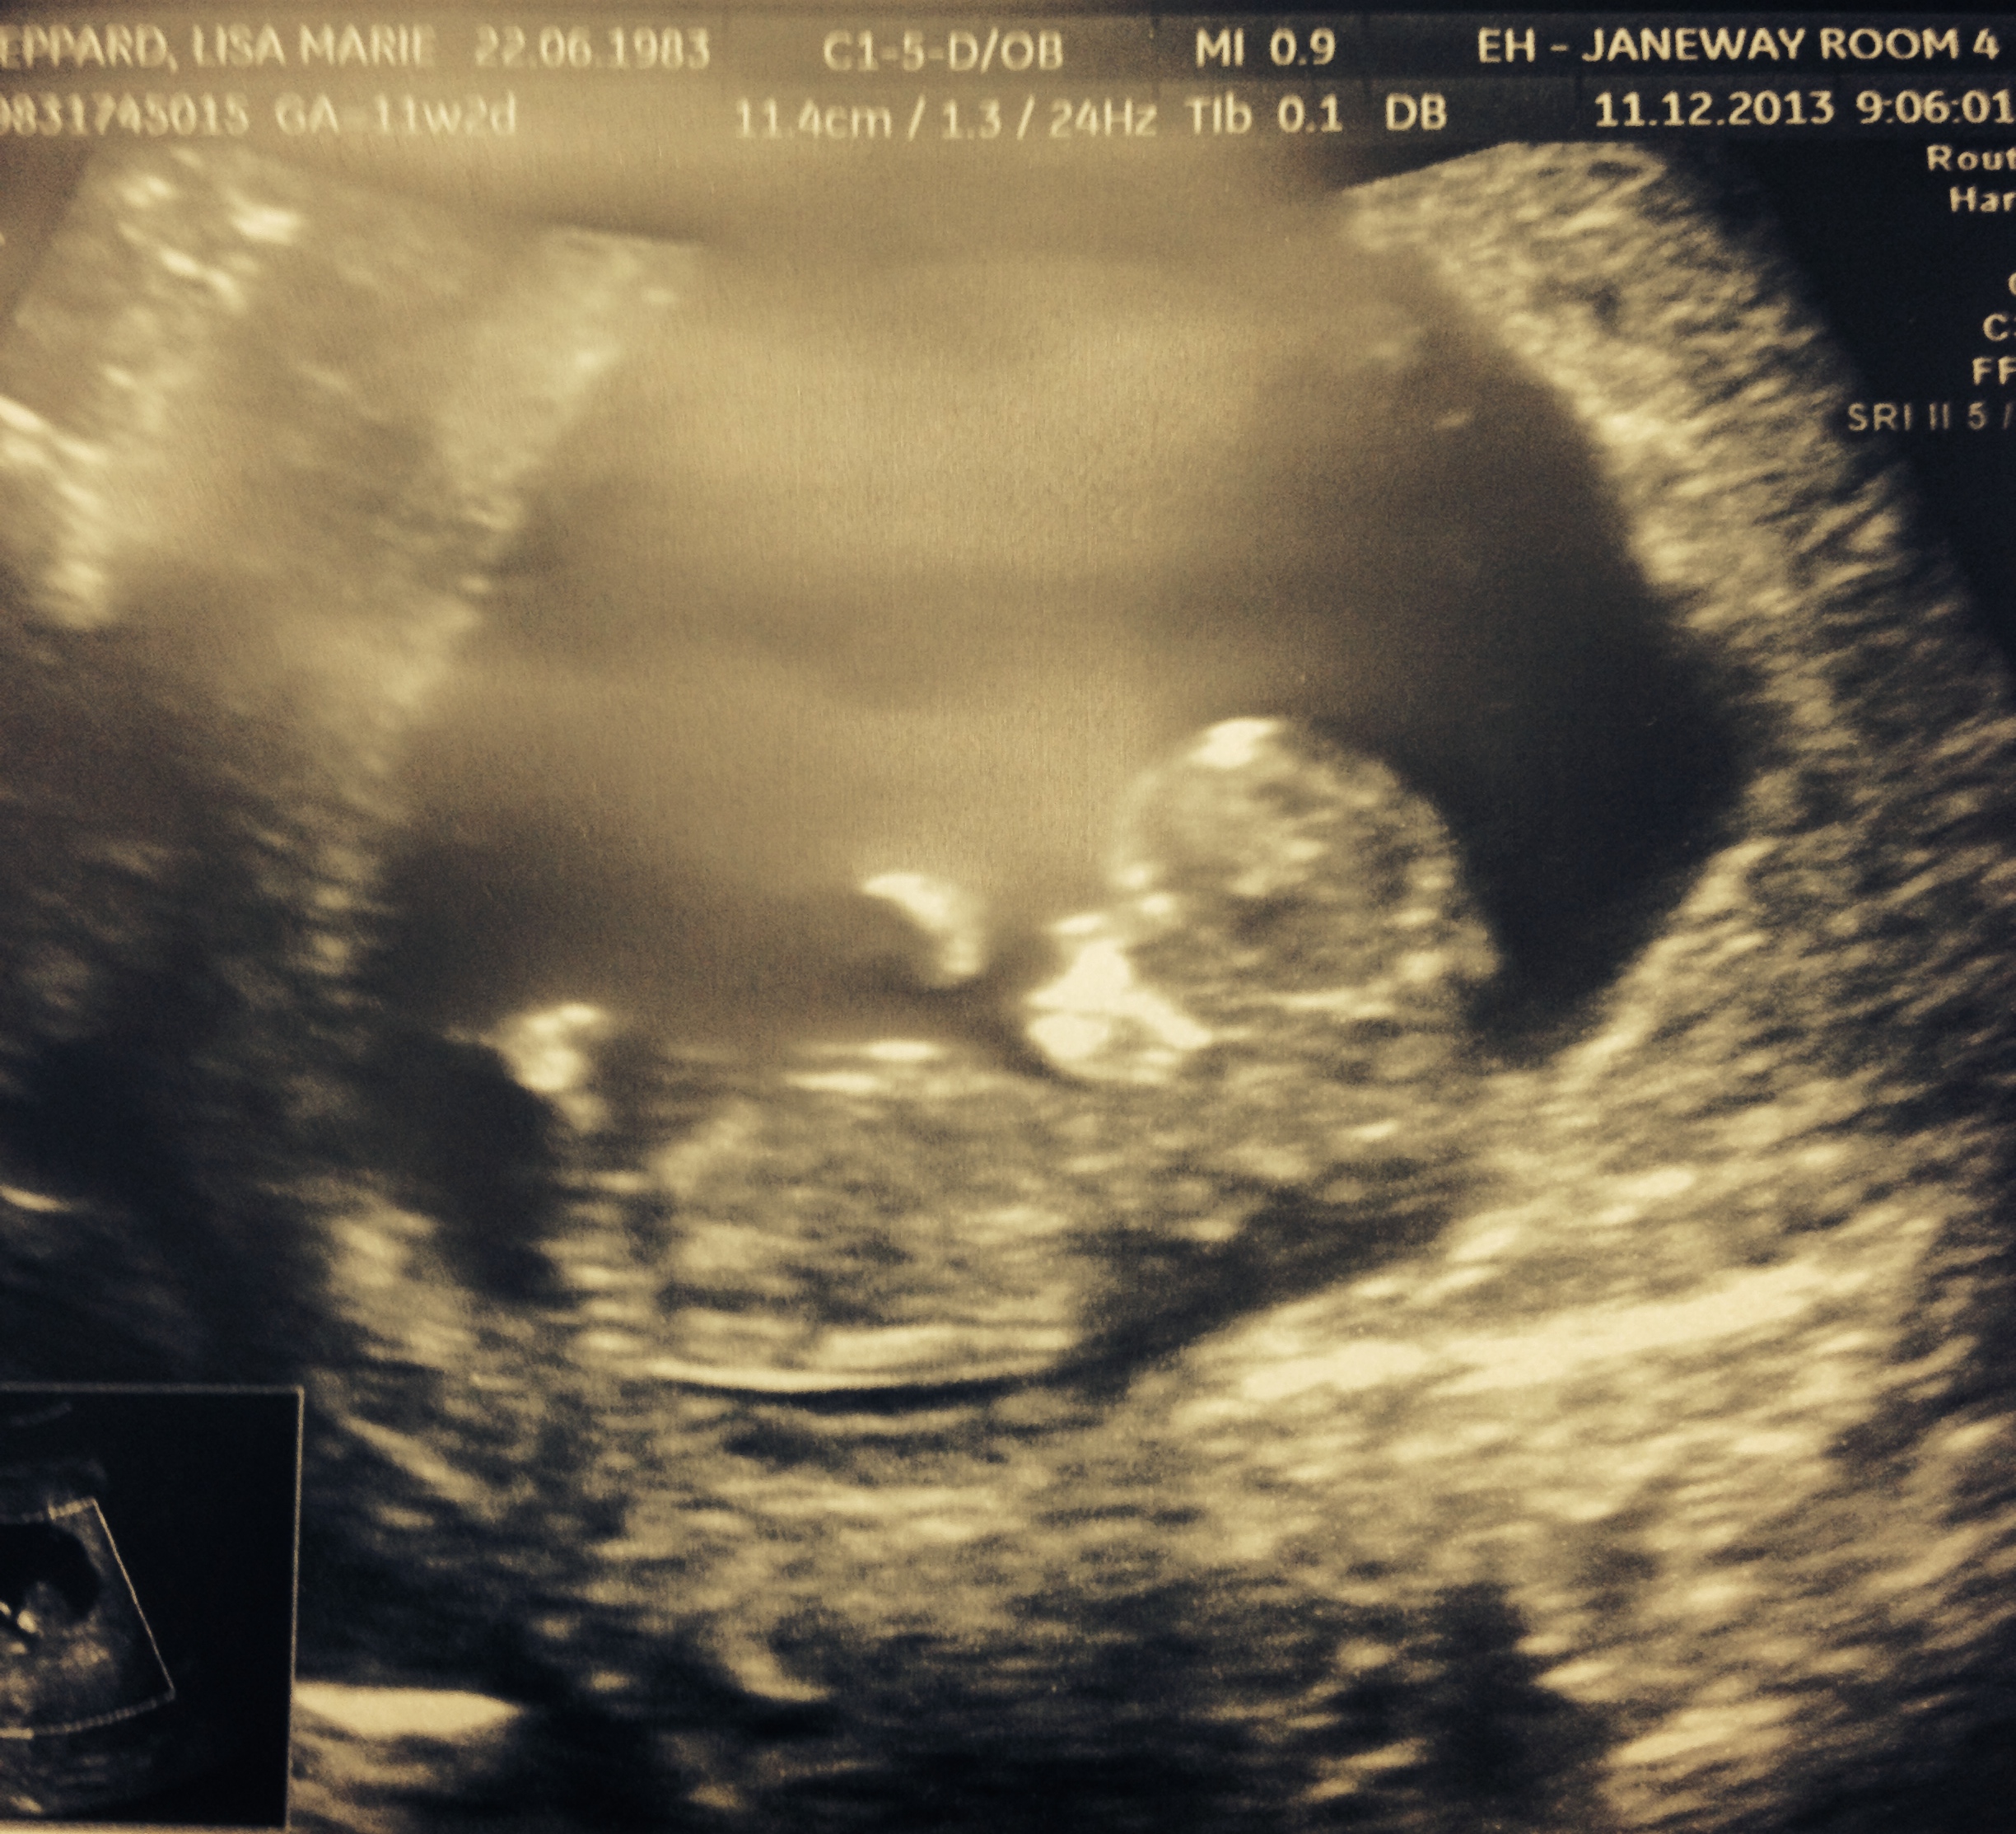

First, we are pregnant with Little Bean #3, due in June 2014!!

So that’s exciting! So far this pregnancy has been filled joy and excitement as well as much sickness! Eye on the prize right?? Mind over Matter?? We are just delighted and for it means the Little Bean is growing and healthy. Patrick and Nathan are so excited and filled with questions. Nate is scared to be a big brother… no longer wants to turn 4 (he turns 4 in June when new baby is due). Where as Patrick is ready to continue on the role as Big Brother… creating a list of things he is going to do and how he is going to help. Family is what its all about really isn’t it?? They are so precious! Here they are the other day at a friends Birthday Party!